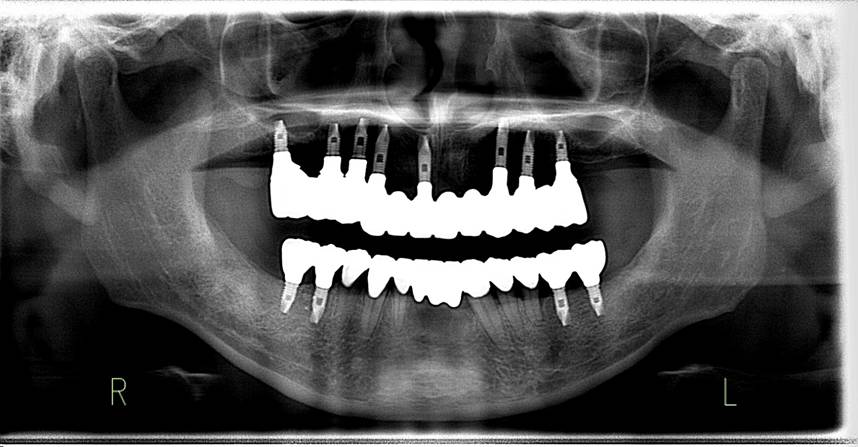

術前パノラマレントゲン写真。根の周りが黒くなり、骨がなくなっていることがわかります

2019年 歯根破折や根面齲蝕のため抜歯した部位をインプラントで補綴しました。ストローマンとスプラインが混在しています。先端の丸井インプラントはストローマンです。

63歳術後のパノラマレントゲン。インプラントはスプラインツイスト